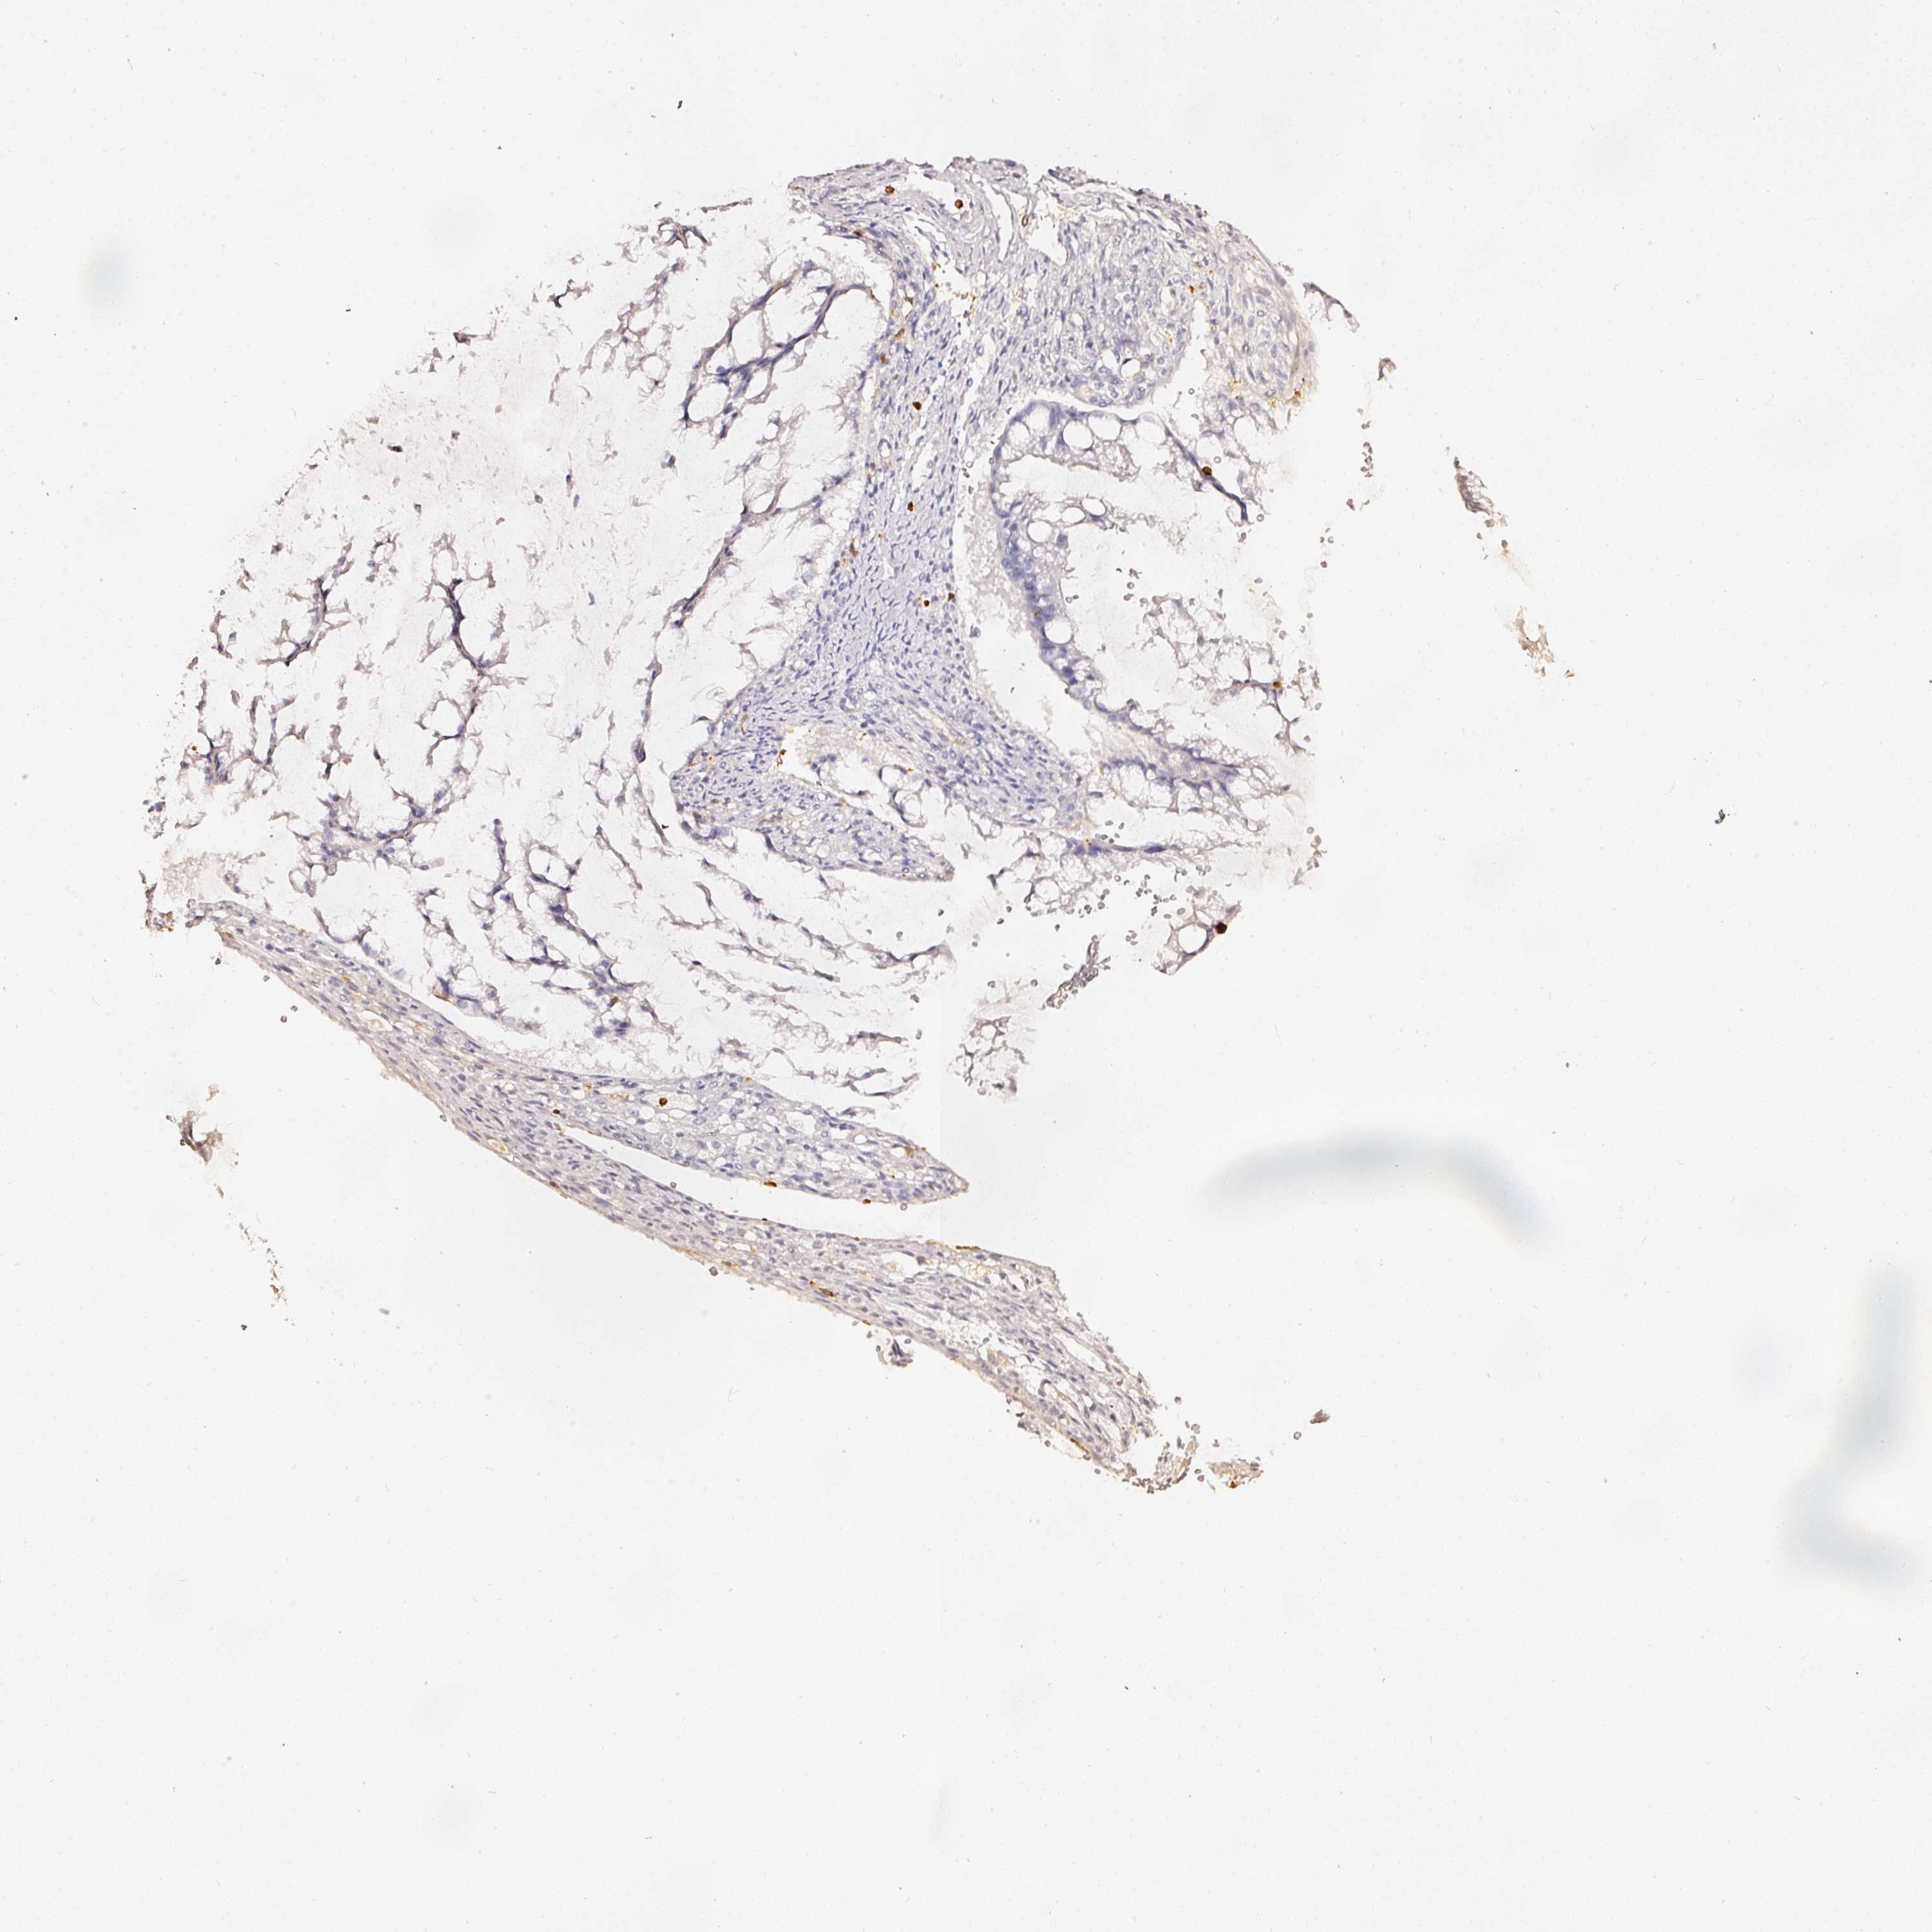

OVARIAN CANCER - Protein expressioni

A mouse-over function shows sample information and annotation data. Click on an image to view it in a full screen mode. Samples can be filtered based on level of antibody staining by selecting one or several of the following categories: high, medium, low and not detected. The assay and annotation is described here.

Note that samples used for immunohistochemistry by the Human Protein Atlas do not correspond to samples in the TCGA dataset.

Antibody stainingi

Antibody staining in the annotated cell types in the current human tissue is reported as not detected, low, medium, or high, based on conventional immunohistochemistry profiling in selected tissues. This score is based on the combination of the staining intensity and fraction of stained cells.

Each image is clickable and will lead to virtual microscopy that enables deeper exploration of all samples and also displays staining intensity scores, fraction scores and subcellular localization as well as patient and tissue information for each sample.

Antibody HPA018849

Antibody HPA019536

Antibody CAB033987

Staining

High

Medium

Low

Not detected

Cystadenocarcinoma, serous, NOS

Carcinoma, endometroid

Cystadenocarcinoma, mucinous, NOS

Carcinoma, NOS